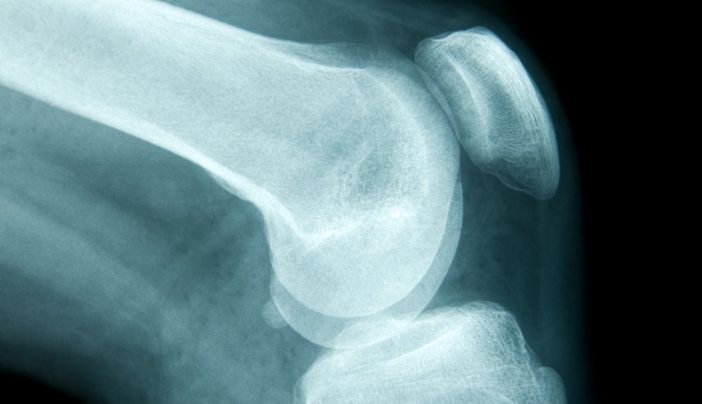

The sooner people adopt healthy lifestyle choices the more they can reduce risk factors for falls and hip injuries later in life. The majority of all hip and spine fractures among older white women can be attributed to underlying bone fragility. In early adulthood healthy habits can boost your peak bone mass.

Risk factors for hip fractures Age is a key risk factor with hip fractures more likely to occur in those aged 65 or older. Breastfeeding protects against hip fracture later in life. 557 18 Colostrum is rich in antibodies that help protect infants from infections.

More specifically there is a 12 decreased risk of hip fracture for every month of breastfeeding. Females are the group most prone to sustaining a hip fracture and therefore to increased mortality rates. In the United States more than 53 million people either already have osteoporosis or are at high risk due to low bone mass.

They calculated a 09 reduction of any fracture from osteoporosis for each month of breastfeeding. Exercise will help you to recover from your fracture but it is important to be cautious and take expert advice.